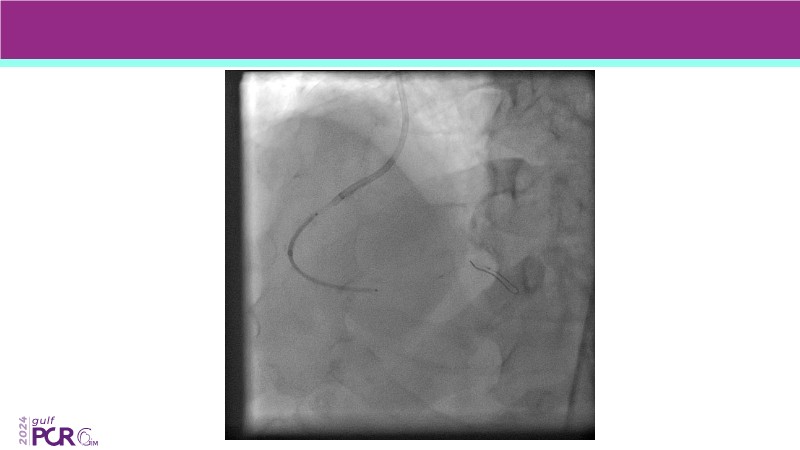

- To discover your next gen complex PCI toolkit with thin strut platforms and dedicated stenting solutions for managing side branch and long diffused lesions

- To learn about the novel Myval THV technology, its key features, procedural and clinical benefits and learn about the clinical data in a vast cohort of patient population